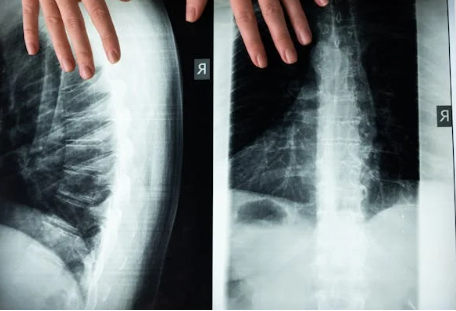

척추측만증은 신체 검사, 엑스레이, MRI 검사를 통해 진단됩니다.

- 엑스레이: 엑스레이는 척추의 측만증 정도를 정확하게 보여줍니다.